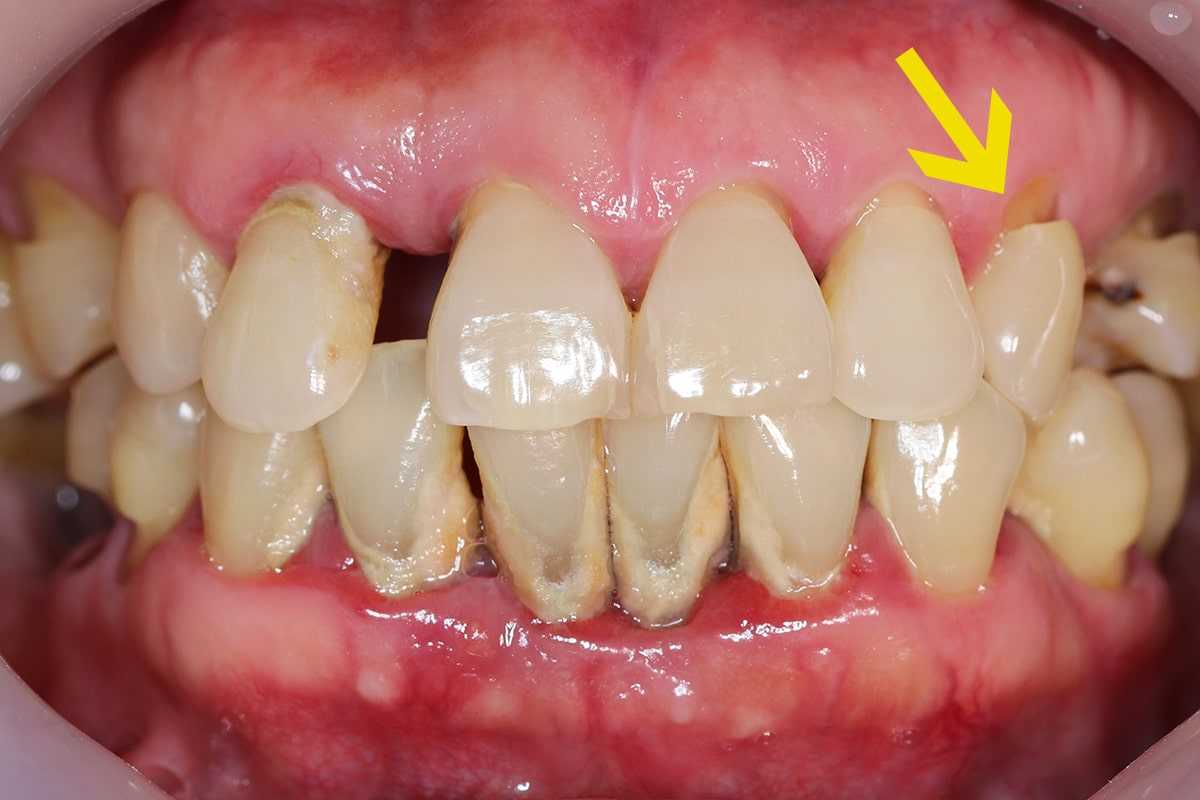

A gumline cavity is a type of tooth decay that occurs at the junction where the tooth meets the gum, often caused by plaque buildup and inadequate oral hygiene.Understanding "Soft Teeth": What You Need to Know